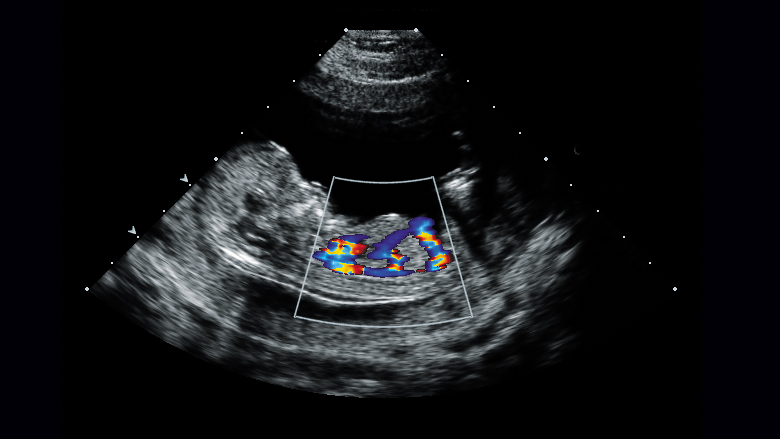

2.- اکوکاردیوگرافی داپلر: برای اندازه‌گیری سرعت جریان خون در حفره‌های قلب و دریچه‌های قلب استفاده می‌شود، همچنین امکان تشخیص جریان خون غیرطبیعی در قلب مانند سوراخ بین اتاقک راست و چپ را با داپلر رنگی فراهم می‌کند. می تواند جهت جریان خون در قلب نوزاد را تجسم کند.

اکوکاردیوگرافی داپلر. این تکنیک داپلر برای اندازه گیری و ارزیابی جریان خون از طریق اتاقک ها و دریچه های قلب استفاده می شود. داپلر همچنین می‌تواند جریان خون غیرطبیعی در قلب را تشخیص دهد که می‌تواند مشکلاتی مانند باز شدن بین حفره‌های قلب، مشکل یک یا چند دریچه از چهار دریچه قلب یا مشکل دیواره‌های قلب را نشان دهد.

داپلر رنگی داپلر رنگی شکل پیشرفته اکوکاردیوگرافی داپلر است. با داپلر رنگی، از رنگ های مختلف برای تعیین جهت جریان خون استفاده می شود. این کار تفسیر تصاویر داپلر را ساده می کند.

داپلر رنگی شکل پیشرفته اکوکاردیوگرافی داپلر است. با داپلر رنگی، از رنگ های مختلف برای تعیین جهت جریان خون استفاده می شود. این کار تفسیر تصاویر داپلر را برای پزشک شما ساده می کند.

جریان خون قلب جنین را مطالعه می کند (مطالعه داپلر طیفی و داپلر رنگی) همانطور که در ویدیوی سمت چپ بالا مشاهده می شود که قوس آئورت را با جریان خون (رنگ قرمز) نشان می دهد.